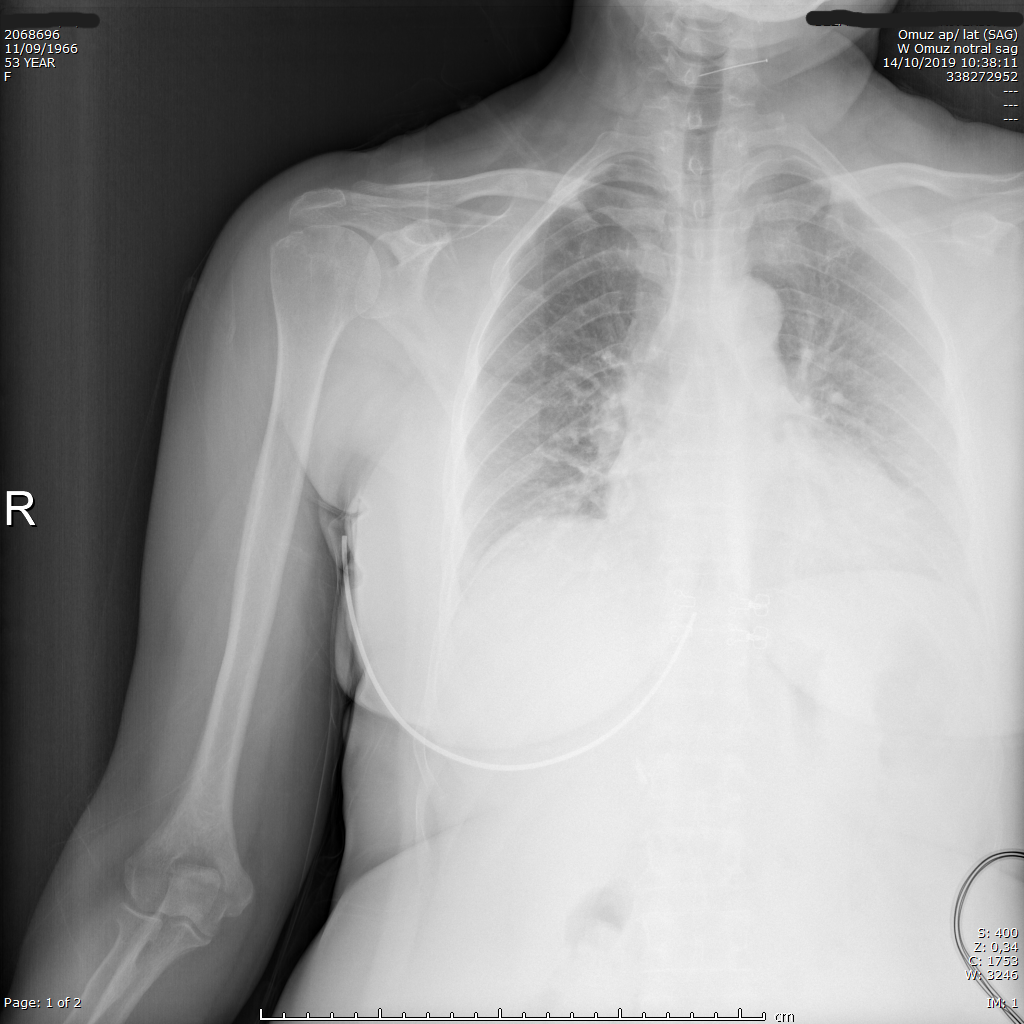

Preoperatif omuz röntgeni — daralmış AHD